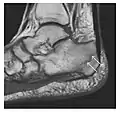

Fatigue fractures are more frequent in women which may be due to the relatively smaller bones of women. Moreover, pregnancy is a well-recognized risk factor for femoral neck fatigue fracture. While fibular and metatarsal fractures have a low risk of complications, other sites including the femoral neck, midanterior tibia, navicular, talar, and other intraarticular fractures are prone to complications such as delayed union, nonunion, and displacement. The site of the insufficiency fracture may be specific to the activity: for example, rugby and basketball players are more prone to navicular fractures, while gymnasts have a higher risk for talar fractures (Figure 7). Long distance runners are at increased risk for pelvic, tibial (Figures 8 and 9), and fibular fractures. In the military, calcaneus (Figure 10) and metatarsals are the most commonly cited injuries, especially in new recruits. Billiard players are at risk for upper limb fractures (Figure 11).[1]

a

b

Figure 7: Fatigue fracture of the talus in a 25-year-old male basketball player with right hind foot and ankle pain, without history of trauma, and a normal initial radiograph (not shown). (a) One-month followup lateral radiograph shows normal appearance. (b) Sagittal T1-weighted MRI shows an irregular fracture line (arrow) within an ill-defined area of hypointensity corresponding to bone marrow edema.[1]